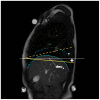

are computed as vertical subtraction of caudal from cranial diaphragm position. The three parameters correspond to the anterior (

), middle (

) and posterior (

) diaphragm part. Points were spread evenly on the diaphragm contour with small constant drift of

and

from the contour margins.